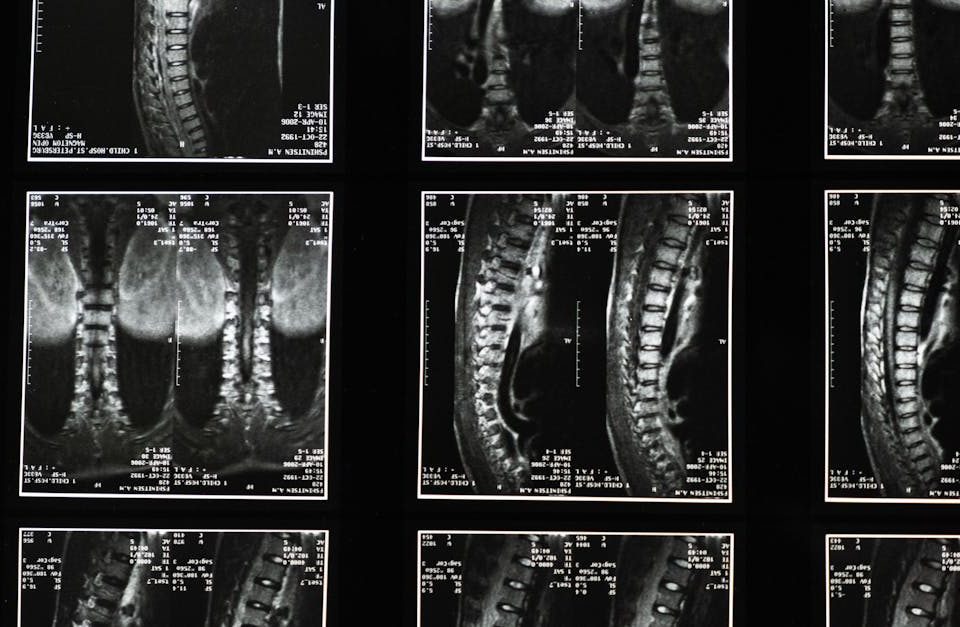

Les innovations dans les traitements de la sténose spinale avec décompression neurovertébrale

EN BREF La décompression neurovertébrale est une méthode thérapeutique avancée conçue pour traiter la sténose spinale, offrant une solution innovante pour soulager les douleurs et améliorer […]

Les signes indiquant que la décompression neurovertébrale pourrait vous convenir

EN BREF La décompression neurovertébrale est une technique non invasive conçue pour soulager les douleuress liées aux problèmes de la colonne vertébrale, notamment les herniés discales […]